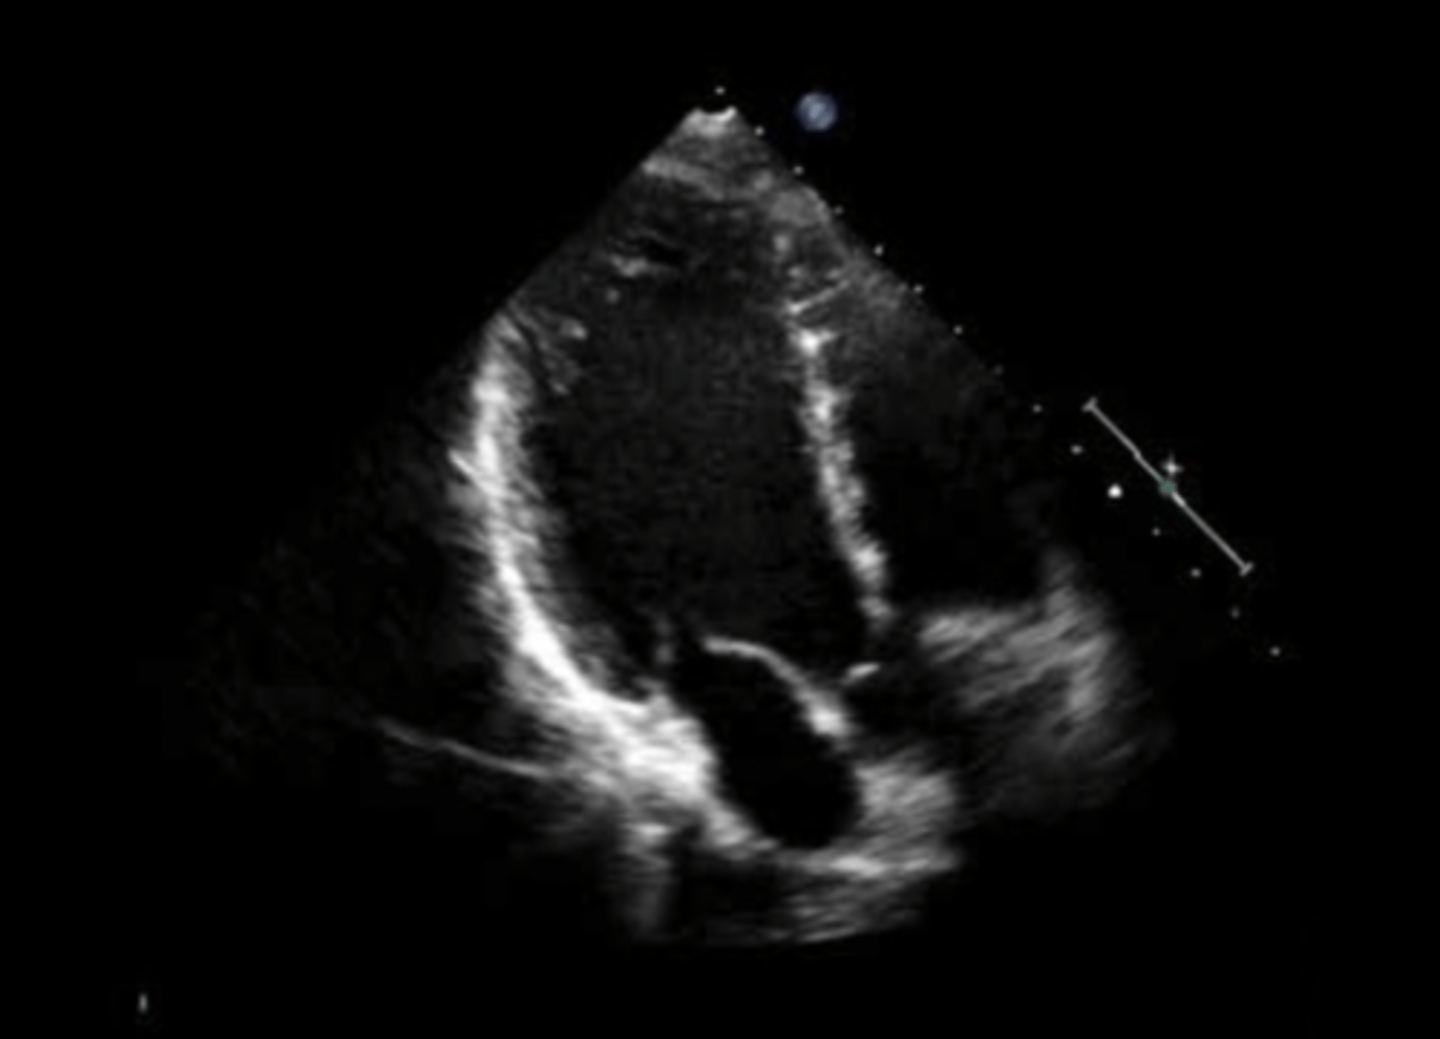

anterior mitral valve leaflet

top leaflet

posterior mitral valve leaflet

bottom leaflet